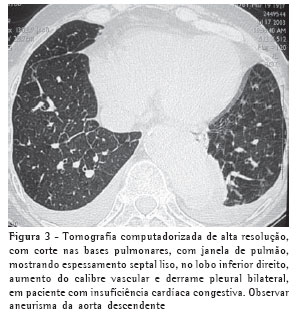

O espessamento dos septos interlobulares ocorreu bilateralmente em 13 casos (Figuras 1, 2, 3 e 4) e unilateralmente em dois, também nos pacientes com mediastinite fibrosante. Em todos os casos o espessamento era do tipo liso.

Derrame pleural foi o terceiro achado tomográfico geral mais comum e, dentre os não parenquimatosos, foi o mais freqüente, tendo sido encontrado em 13 pacientes (87%), e ocorrido predominantemente de forma bilateral (n = 11) (Figuras 1, 2 e 3). Dentre os 11 casos de derrame bilateral, nove pacientes tinham derrame pleural assimétrico, com predomínio à direita. Em dois casos foi encontrado derrame pleural somente à direita.

O calibre vascular mostrou-se aumentado em sete casos (44%) (Figura 3).